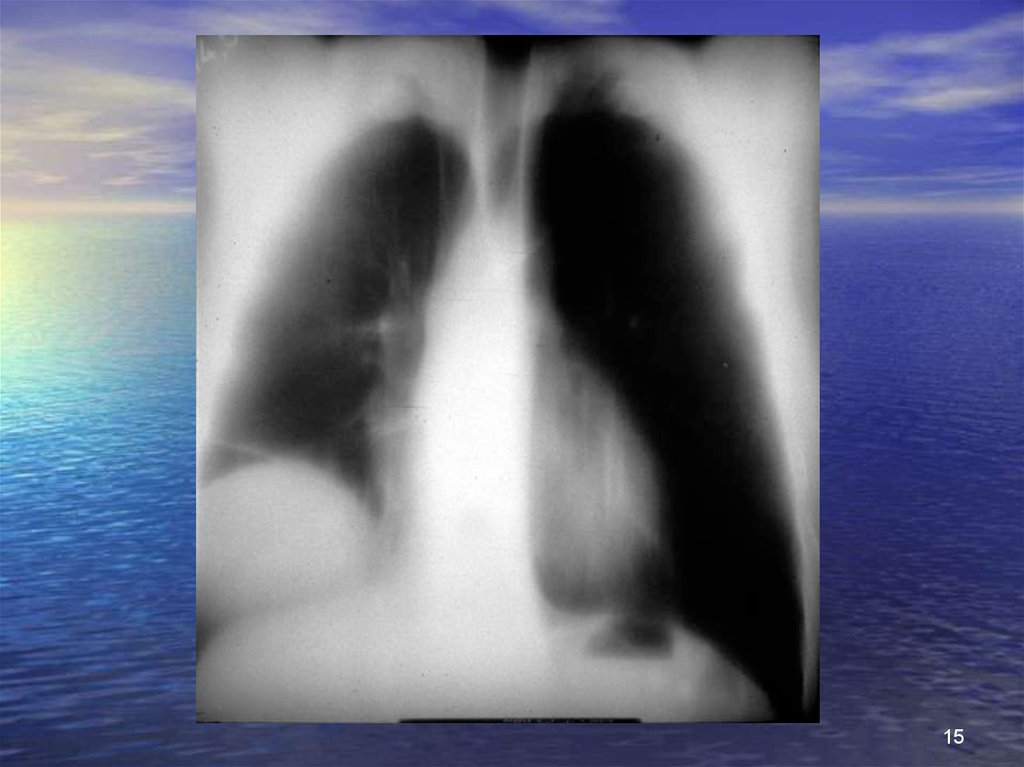

Разрыв диафрагмы (3)

рентгенологические исследования

• Очевидное повреждение диафрагмы

картина повышенной гидроаэрогенности внутри грудной клетки

грыжа с содержимым из полых органов

установка зонда;

ввести водорастворимый контраст;

картина затемненная: органы паренхимы

• Повреждения с трудной интерпретацией

поднят купол диафрагмы плохо визуализируется;

ателектазы;

гемо- или пневмоторакс;

затемнения базы легких